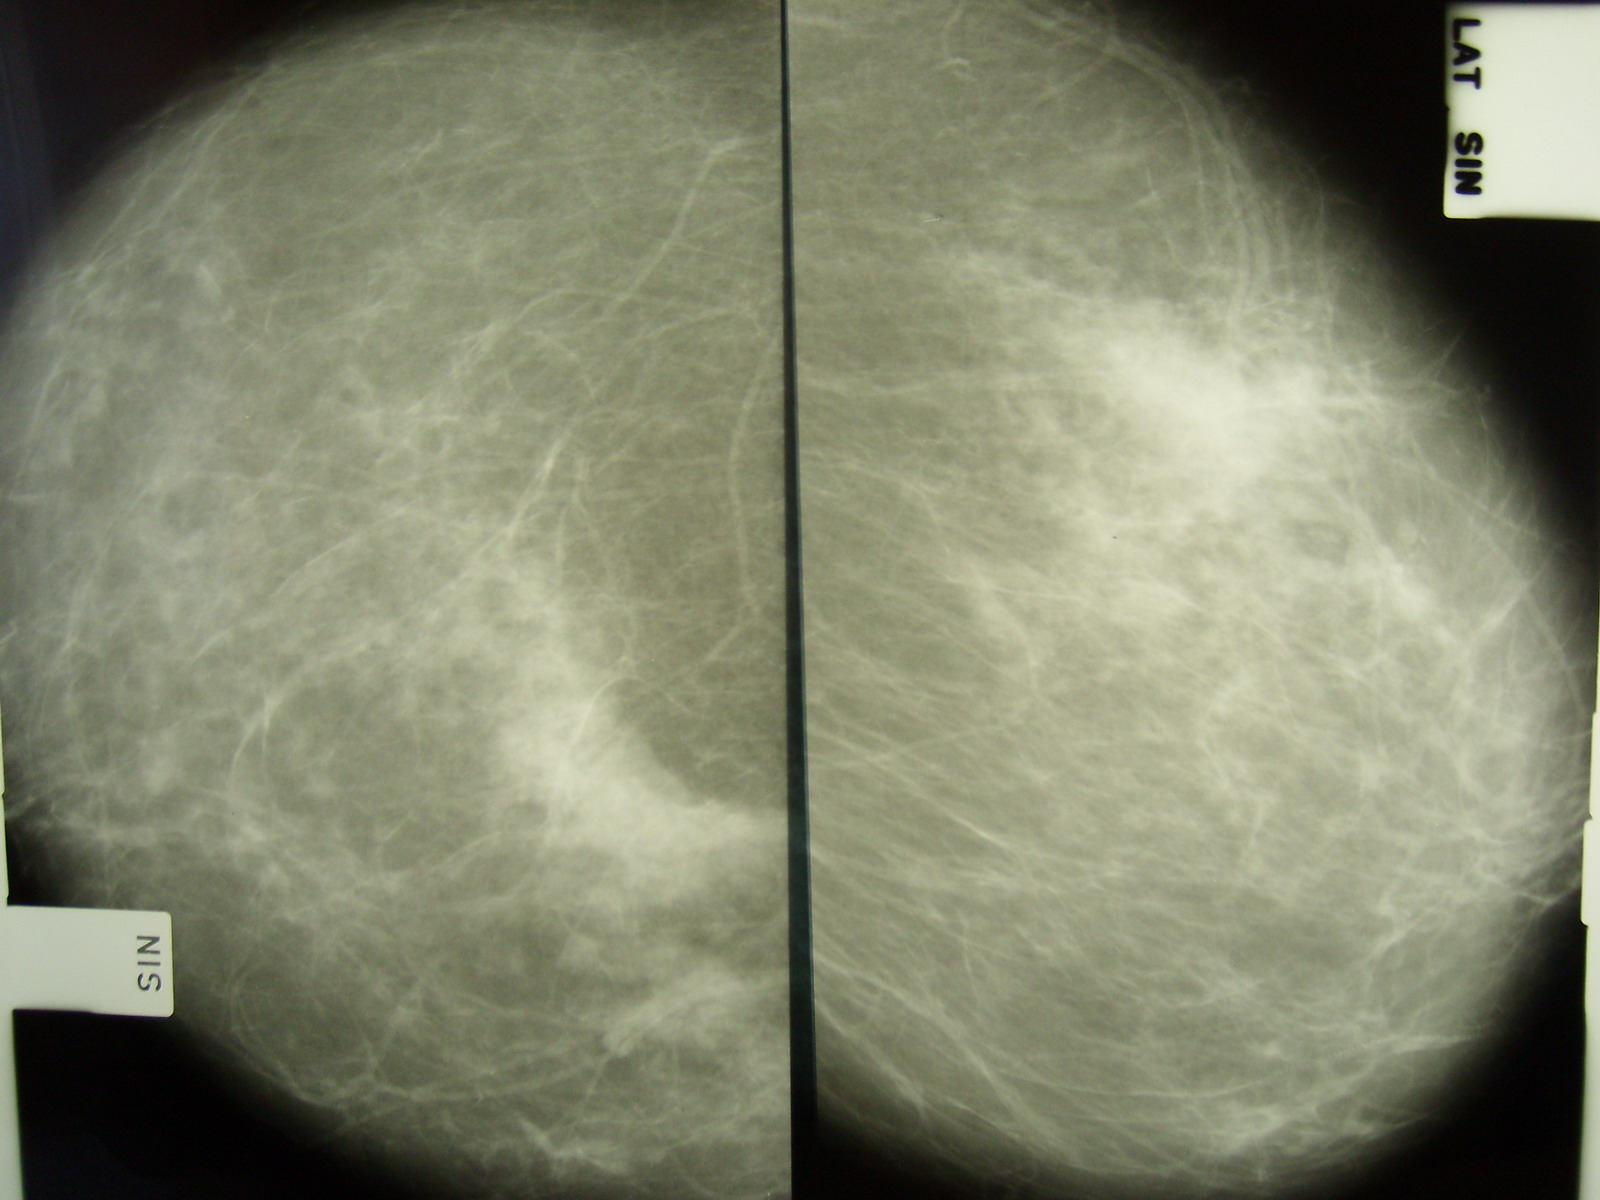

Фиброаденома молочной железы - доброкачественное образование, которое часто встречается у женщин. Оно может быть обнаружено при помощи различных методов диагностики, включая маммографию. Ниже представлены фотографии, помогающие понять, как выглядит данное заболевание.

Фиброзно-кистозная мастопатия рентген молочных желез

Маммография и ее роль в диагностике фиброаденомы молочной железы

Маммография - это рентгенологическое исследование молочных желез. Оно позволяет выявить различные изменения в тканях, включая фиброаденому. На маммограммах можно увидеть структурные особенности опухоли и отследить ее динамику во времени.